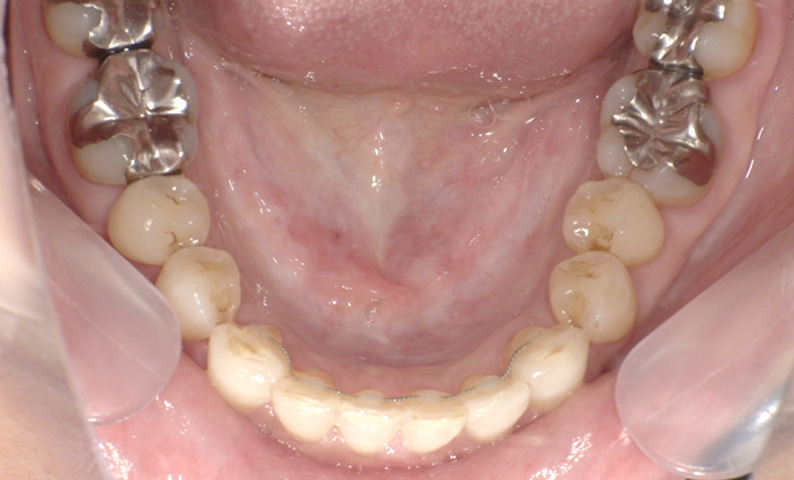

症例_001 「出っ歯」症例

治療期間:13ヶ月金額:54万円+税20代女性出っ歯捻転歯

| Before | After |

|---|---|

|